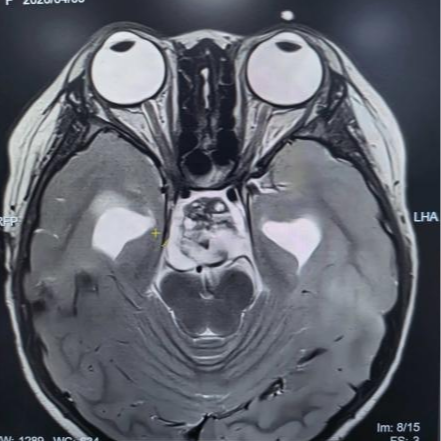

术前核磁共振检查

为精准掌握肿瘤情况,团队为欢欢完善了垂体MRI平扫+增强检查及相关激素水平检测。结果显示:肿瘤体积超过4厘米,形如鸡蛋,已严重压迫视神经与垂体,突入第三脑室,并与周围重要神经血管结构紧密粘连。颅咽管瘤是一种起源于颅底的先天性良性肿瘤,因体积大、位置深,且毗邻下丘脑、视神经、垂体等重要结构,手术切除难度极高,稍有不慎就可能导致失明、终身内分泌紊乱甚至有生命危险。